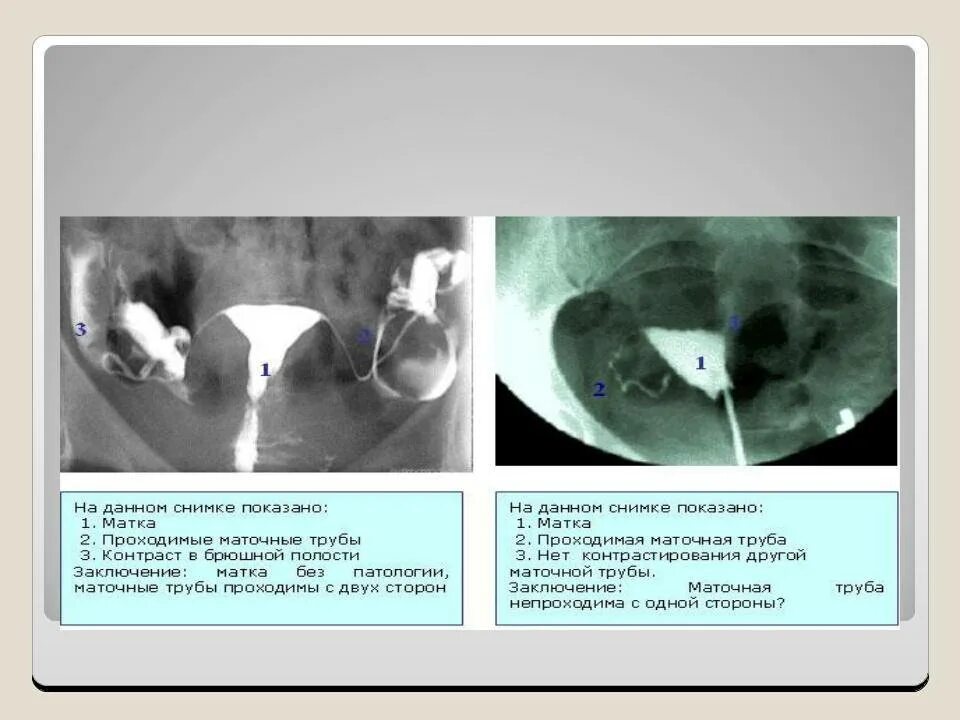

Операции матки и трубы